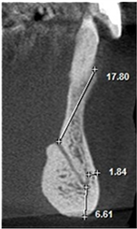

The following measurements were performed: longest width of the genial canal (W) or (D); longest length of the genial canal in relation to the alveolar bone crest (L) or (L1); (D1) or (L2), which was performed between the uppermost portion of the genial plexus and the alveolar bone crest (for dentate patients the reference was the buccal bone crest); shortest distance from the genial plexus to the buccal cortical bone (D2) or (L3), which was performed between the most vestibular portion of the genial plexus and the buccal cortical bone; (D3) or (L4), which was performed between the lowest portion of the genial plexus and the cortical part of the mandible base (Figures 1(B)-(D)).

Figure 2(A) is the initial parasagittal tomographic image of a dentate patient. Figure 2(B) Is the tomographic image of the paranasal sinuses in which the largest. Length of the genital canal (L or L1). Figure 2(C) is the parasagittal tomographic image in which the largest. The diameter of the genital plexus (W or D). Figure 2(D) is the tomographic image in which the measurement of the shortest distance from the plexus to alveolar bone crest (D1 or L2), shorter distance from the plexus to the buccal cortex (D2 or L3), and less distance from the plexus to the base of the mandible (D3 or L4).

Figure 1. Tomographic images, diameters and distances of the canal and plexus. (A) Parasagittal tomographic image; (B) Canal diameter; (C) Distance from the genial plexus to the cortical bone; (D) Initial parasagittal tomographic image, central incisor tooth. Source: Own Authorship. Caption: Parasagittal tomographic image measuring the length (A) canal diameter (B) and distances as follows: (L1) of the genial canal; (L2) distance from the genial plexus to the alveolar bone crest, (L3) distance from the genial plexus to the buccal cortical bone and the base of the mandible (L4) (C), initial parasagittal tomographic image (D). Figure 1 (A) Parasagittal section of the CBCT used to perform measurements. (B) Longest width of the genial canal (W). (C) longest length of the genial canal (L). (D) Shortest distance from the genial plexus to the alveolar bone crest (D1); shortest distance from the genial plexus to the buccal cortical bone (D2); shortest distance from the genial canal relative to the base of the mandible (D3).